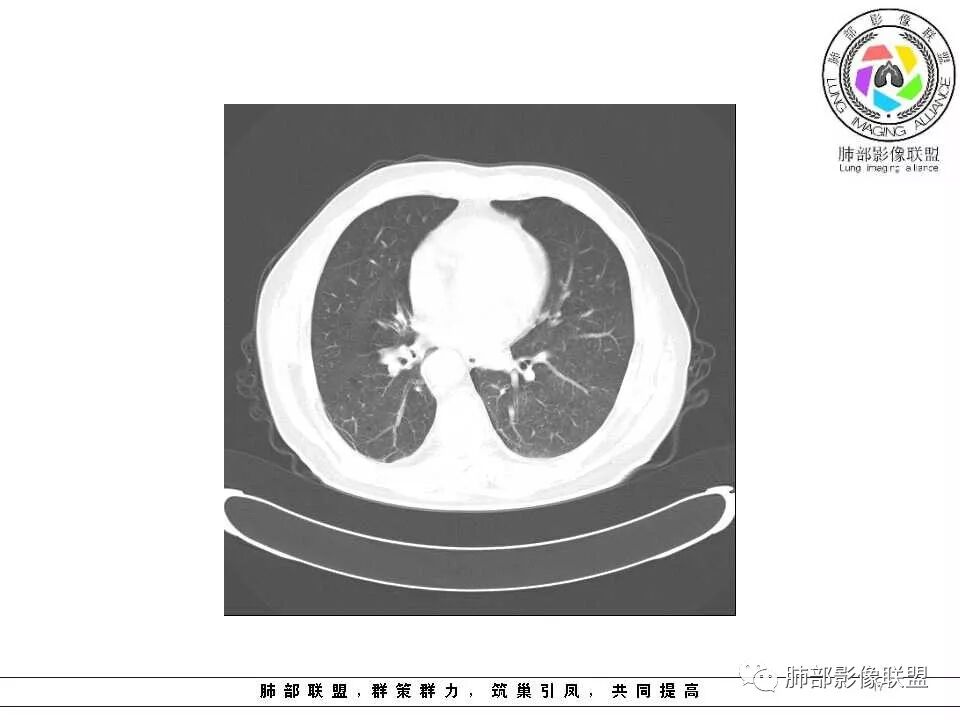

临床特点老年男性、有咯血一个月

影像学特点:肺气肿背景下在大概一年的时间里出现了一个光滑的小结节,因为图像给的不是太薄,与支气管的关系判断不清,从结节周围出现斑片状炎症来判断,应该考虑结节位于支气管内,周围是阻塞性炎症,这样比较容易解释咯血

纵隔窗上似乎结节内可见点状高密度影,同时没有明显肿大淋巴结

所以我考虑支气管内的恶性肿瘤,类癌可能大。

老年男性,肺气肿基础。约一年时间出现左肺上叶舌段支气管近端结节影,远端斑片样阴影,边缘模糊。考虑近端恶性占位,远端有阻塞性炎症。

老年男性,两肺可见小叶中央型肺气肿,提示应该有抽烟史。2016年片,右肺门支气管稍模糊,考虑慢性感染,纵膈淋巴结稍大。但2017年左肺上叶新发占位,堵塞支气管,引起局部肺不张伴感染,且纵膈淋巴结较2016年变大,患者同时伴有咯血,考虑恶性。鳞癌?类癌?小细胞?

肺气肿背景,2016年左肺上叶上舌段见微结节,2017年5月左肺结节增大,密度均匀,边缘光滑锐利,与邻近血管关系密切,血管贴壁走行,外侧见尖状突起,下舌段片状影,沿着支气管走行,内有粘液栓,考虑鳞癌,鉴别小细胞肺癌。

肺气肿背景,2016年左肺上叶上舌段见微结节,一年后左肺结节增大,密度均匀,边缘光滑、膨隆,似见小分叶,下舌段片状影,沿着支气管走行,内,老年患者,咯血1月。考虑恶性病变并阻塞性肺炎,鳞癌?注意鉴别结核。

老年男性,咯血1月,肺气肿背景,16年左肺上叶舌段结节,左肺门疑似淋巴结肿大,呈结节感。17年左肺上叶舌段见沿支气管走行分布结节 远端阻塞性肺炎,左肺门淋巴结肿大明显,首先考虑恶性病变,鳞癌?类癌?

前次片2016年4月20相应位置就有小点状病灶,2017-5-15呈结节影改变,边界膨隆,远端阻塞炎性改变,考虑肺癌,鉴别炎性结节!